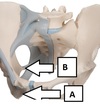

1B What nerve passes through foramen A

Foramen A- lesser sciatic foramen

Sciatic nerve

11A. Identify the specific part of the bone labelled A

Ischial tuberosity

11B. Identify the specific part of the bone labelled B

Ischial spine